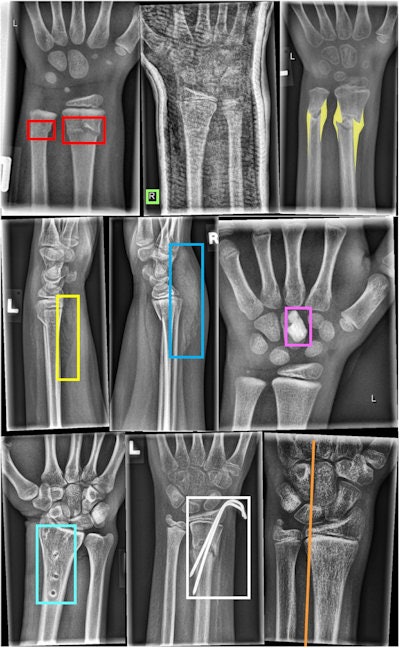

Between March 2018 and February 2022, several pediatric radiologists with between six and 29 years in musculoskeletal radiology validated all annotated dataset images. They placed lines, bounding boxes, or polygons to mark pathologies like fractures or periosteal reactions, as well as tagged general image characteristics.